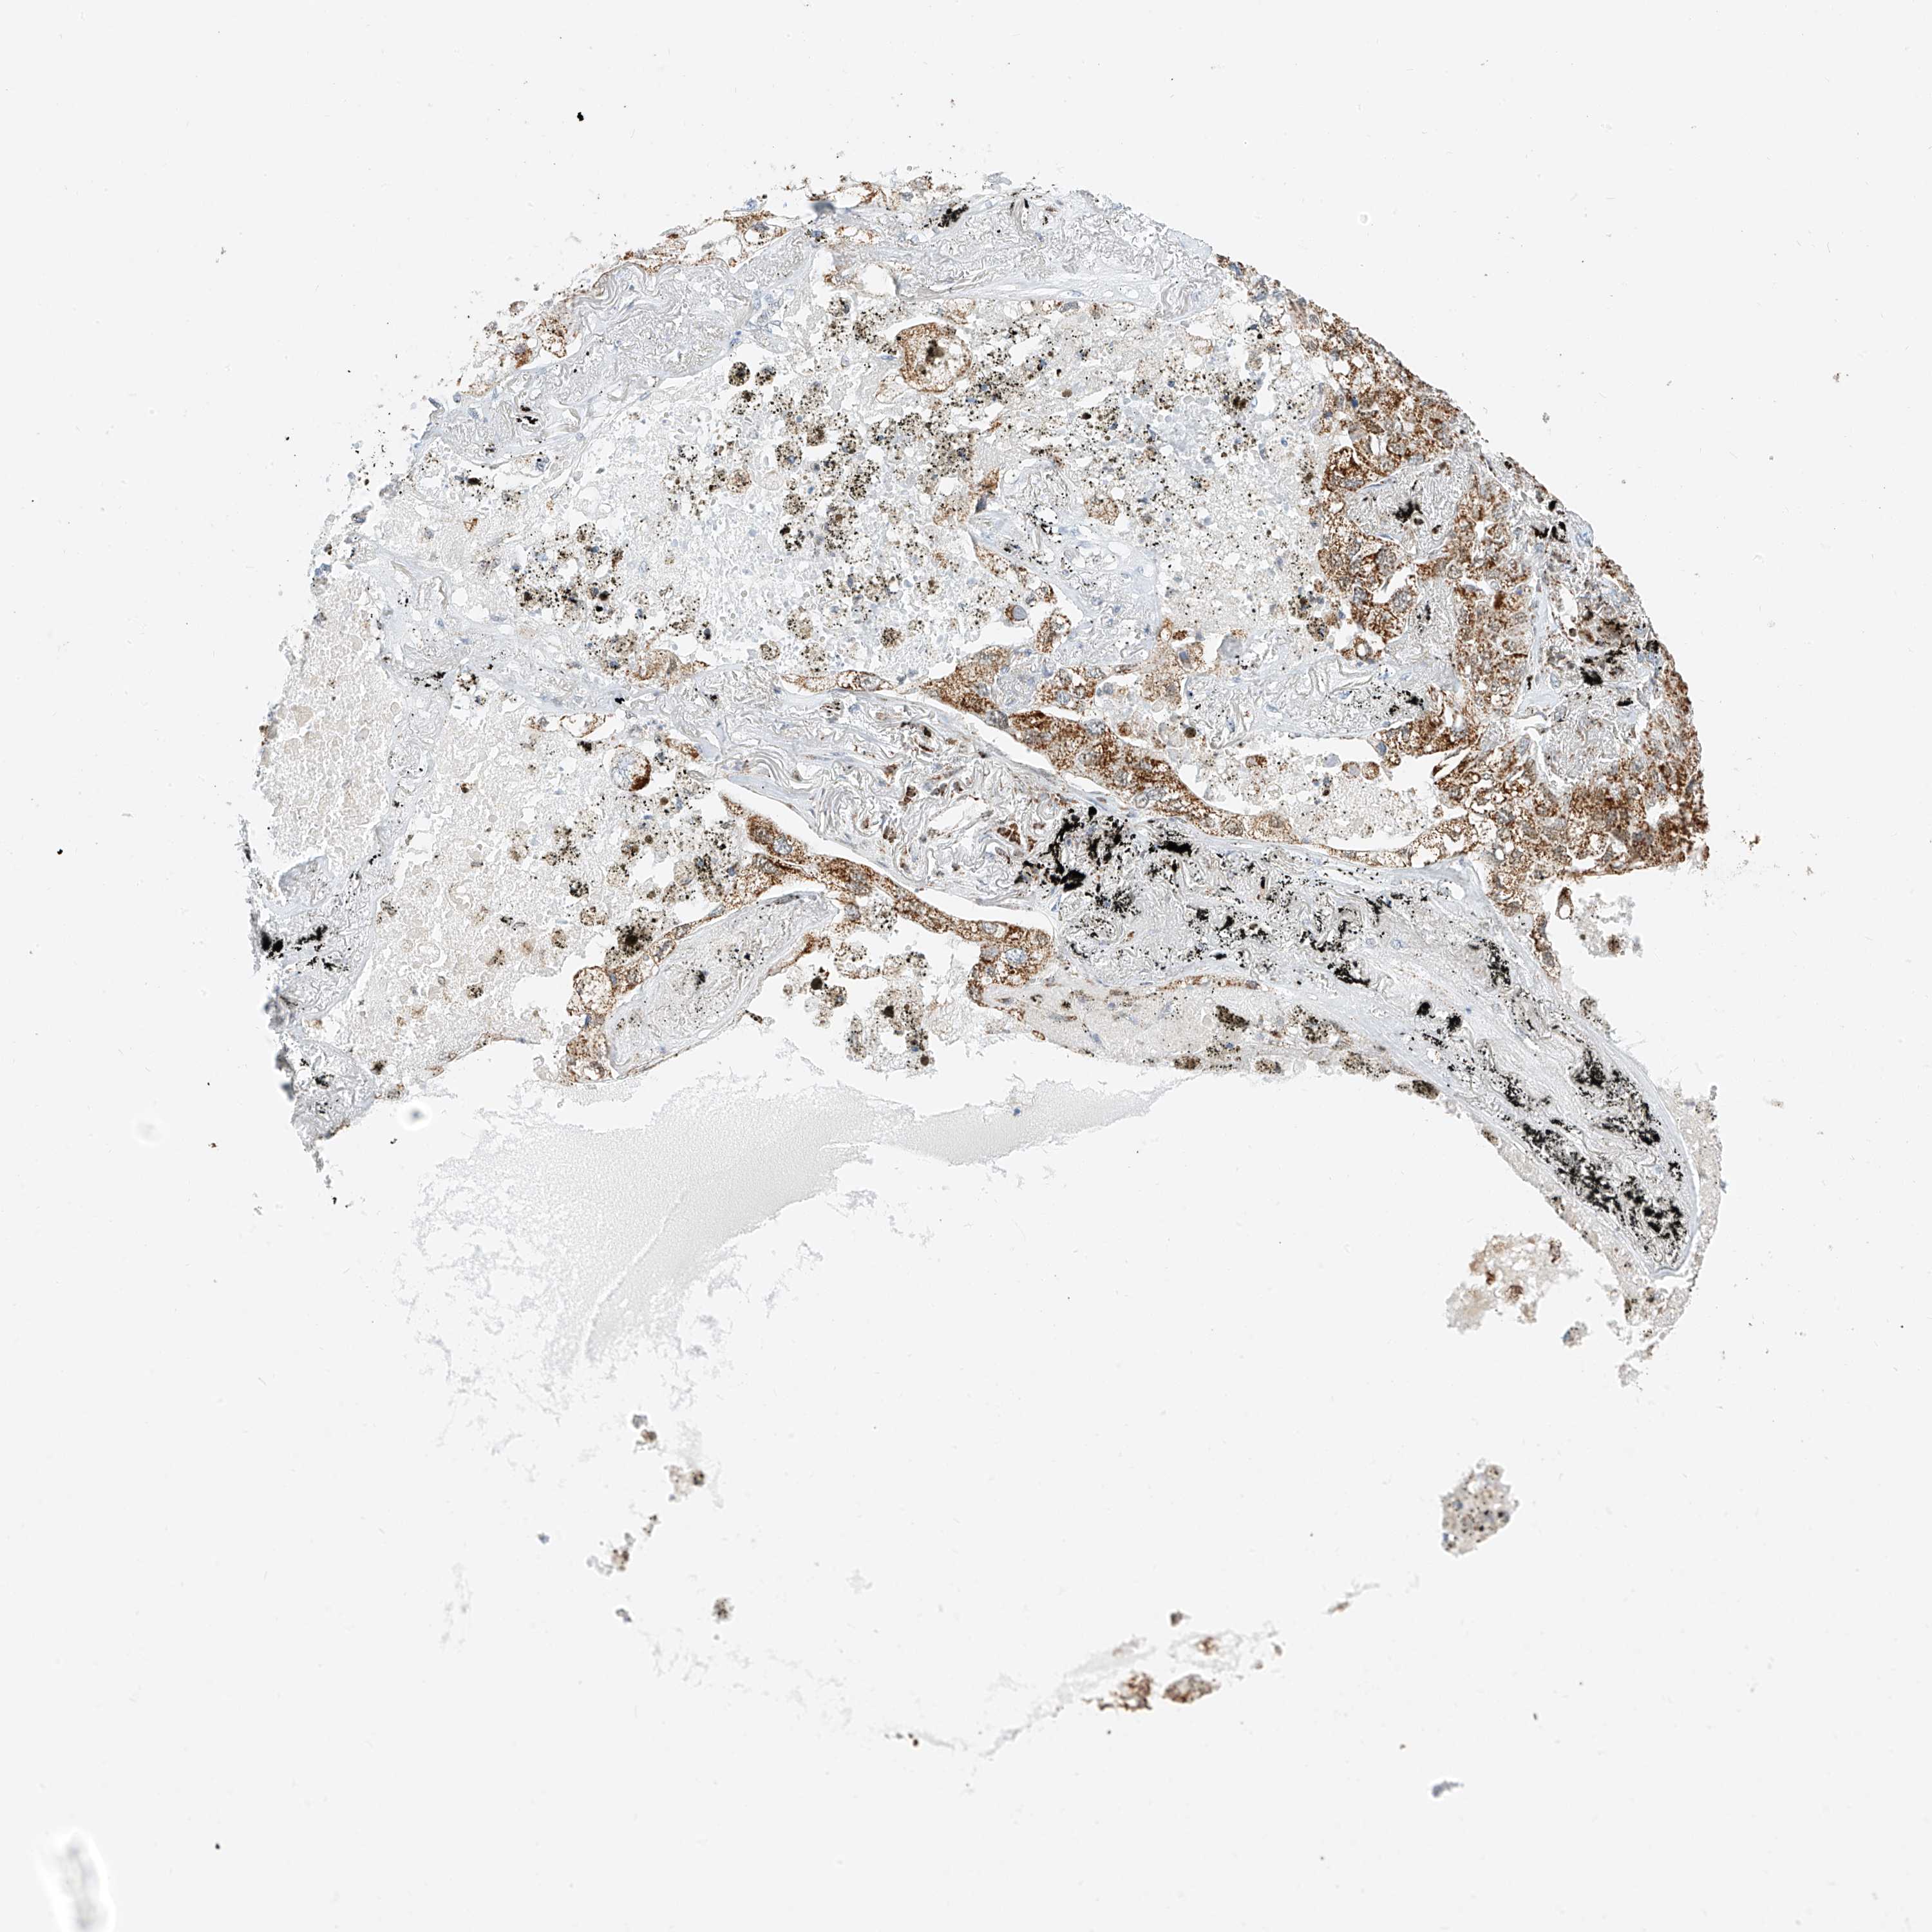

CANCER LUNG CANCER Show tissue menu

LUAD TCGA LUAD VALIDATION LUSC TCGA LUSC VALIDATION PROTEIN LUAD CPTAC PROTEIN LUSC CPTAC PROTEIN EXPRESSION

ANTIBODIES

AND

VALIDATION